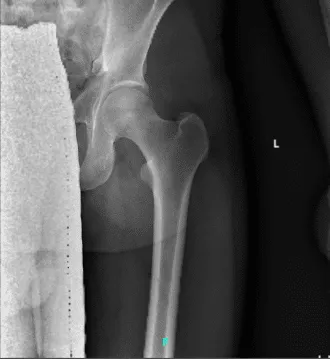

Presentó los resultados de la radiografía del hombro derecho que mostraron artropatía de la articulación acromioclavicular. En la cadera izquierda, las radiografías han mostrado una leve sobrecobertura acetabular. Para la columna cervical, reducción leve del espacio discológico.

También presentó los resultados de la resonancia magnética para su hi-húper izquierdo, que mostraron desgarro del labrum posterior superior en la posición de las 10 a las 11 en punto. Lesión de Morel Lavalee en los tejidos subcutáneos posteriores superficiales al tensor de la fascia lata.

Recomiendo consulta con el ortopedista. Pérdida de cartílago y cambio quístico en el acetábulo posterior superior. Sobrecobertura acetabular. Bursitis trocantérica mayor izquierda.

Radiografía 2-3 vistas de la cadera izquierda

Resonancia magnética de cadera izquierda sin contraste